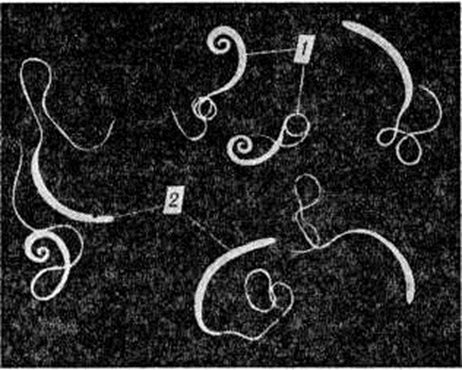

ТрихоцефалёзТрихоцефалёз (Trichocephalosis) — гельминтоз из группы нематодозов, характеризующийся нарушением функции желудочно-кишечного тракта и нервной системы. Трихоцефалёз впервые описан Дж. Морганьи в 1761 год Распространен повсеместно, особенно во влажных зонах умеренного, субтропического и тропического пояса; местами им заражено до 90% населения. Чаще болеют дети и подростки в возрасте от 5 до 15 лет. Возбудитель — власоглав — Trichocephalus trichiurus (L., 1771) Blanchard, 1895 из семейство, Trichocephalidae Baird, 1853; паразитирует только у человека. Нематода белого, иногда слегка красноватого цвета, передний отдел тела тонкий, длинный, задний — короче и утолщен; у самца задний отдел загнут в виде спирали, у самки — изогнут дугообразно (рисунок). Длина самца 30— 45 миллиметров, самки — 35—55 миллиметров. Яйца гельминта размером 50—54 × 22— 23 микрометров, жёлтого или коричневого цвета, бочонковидной формы с пробочками на полюсах. Самка власоглава откладывает яйца, в которых процесс их созревания (формирование личинки) завершается в окружающей среде. При t° 30° и высокой относительной влажности в яйцах через 25—29 дней развивается подвижная личинка, после чего яйца становятся инвазионными (смотри полный свод знаний: Инвазия). Инвазионные яйца власоглавов могут длительное время (до 3 лет) сохраняться жизнеспособными в почве, с чем связано их накопление и длительное существование в очагах Трихоцефалёз Яйца стойки к воздействию дезинфицирующих средств. При заглатывании человеком инвазионных яиц из них в кишечник выходят личинки, которые внедряются в ворсинки слизистой оболочки кишки, где остаются от 3 до 10 суток По истечении этого срока личинки опять выходят в просвет кишки и фиксируются головным концом на её стенке. Через l½—2 месяцев паразиты становятся половозрелыми и самки начинают откладывать яйца. Власоглавы локализуются в слепой кишке, аппендиксе, восходящей ободочной кишке, а при интенсивной инвазии — на всем протяжении толстой кишки, изредка в нижнем отделе тонкой кишки. Паразитирование власоглавов может длиться 56 лет. У одного больного может быть один паразит, несколько десятков, реже сотни и даже тысячи. Источником возбудителей инвазии власоглавами является только человек. Заражение человека трихоцефалезом происходит при проглатывании инвазионных яиц власоглава с загрязнёнными продуктами питания и водой. Особенно часто это происходит при употреблении в пищу сырых овощей и ягод, выращиваемых на почве, удобряемой фекалиями человека. Возможно заражение через руки, загрязнённые инвазионными яйцами. Наиболее часто заражаются Трихоцефалёз в период обработки почвы, сборе ранних овощей и клубники, то есть весной и летом. Наибольшему риску заражения подвергаются дети из-за недостатка у них гигиенические навыков. Обычно реакция организма человека на внедрение власоглавов мало выражена, но иногда в стенке толстой кишки возникают инфильтраты, состоящие преимущественно из эозинофилов, плазматических клеток и частично лимфоидных элементов. Могут отмечаться мелкие кровоизлияния и эрозии на слизистой оболочке кишки, а при гнездном расположении паразитов — формироваться опухолевидные гранулематозные разрастания. Продукты обмена веществ гельминтов вызывают сенсибилизацию организма больного. Травматизация стенки кишки может способствовать проникновению в неё бактерий (например, кишечной палочки и другие) с развитием местного воспалительного процесса: колит (смотри полный свод знаний), аппендицит (смотри полный свод знаний), тифлит (смотри полный свод знаний), проктосигмоидит (смотри полный свод знаний: Колит). Раздражение интерорецепторов обусловливает возникновение патологический нервных импульсов, вызывающих расстройства функций кишечника и желудка. Стойкого иммунитета после перенесения Трихоцефалёз не возникает, о чем свидетельствуют повторные заражения Трихоцефалёз, особенно детей. В клинические, течении Трихоцефалёз значительную роль играет интенсивность инвазии и реактивность организма больного. Заражение единичными паразитами обычно не вызывает выраженных болезненных явлений. Больные Трихоцефалёз обычно жалуются на общее недомогание, повышенную утомляемость, понижение (реже повышение) аппетита, слюнотечение, тошноту, изредка рвоту, тупые боли в животе, чаще в правой подвздошной и эпигастральной областях. Приблизительно у половины больных отмечаются запоры или чередование их с поносами. При поносах в фекалиях может быть примесь слизи. |

Рис | ||